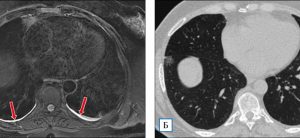

Спаечный процесс в малом тазу

Несмотря на длительный период исследований спаек в брюшной полости, особенно в тазу, до сих пор не выработано единых взглядов на механизм их образования и профилактики. По данным американских исследователей, смертность от кишечной непроходимости, вызванной спаечным процессом, составляет около 2000 человек в год. Частота спаек таза у женщин в 2,6 раза выше, чем у мужчин, а …